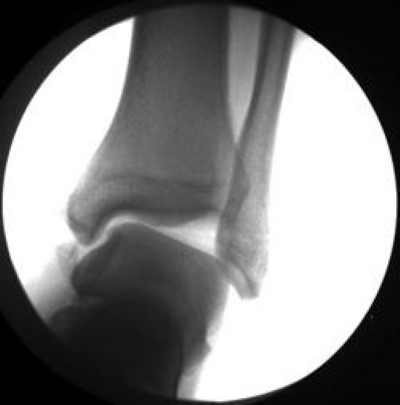

Ankle instabillity

This X-ray shows extreme instability of the ankle.

Espinosa N, Bluman EM: Lateral Ankle Ligament Reconstruction Using Allograft, in Flatow E, Colvin AC, eds: Atlas of Essential Orthopaedic Procedures. Rosemont, IL, American Academy of Orthopaedic Surgeons, 2013, pp 349-355.